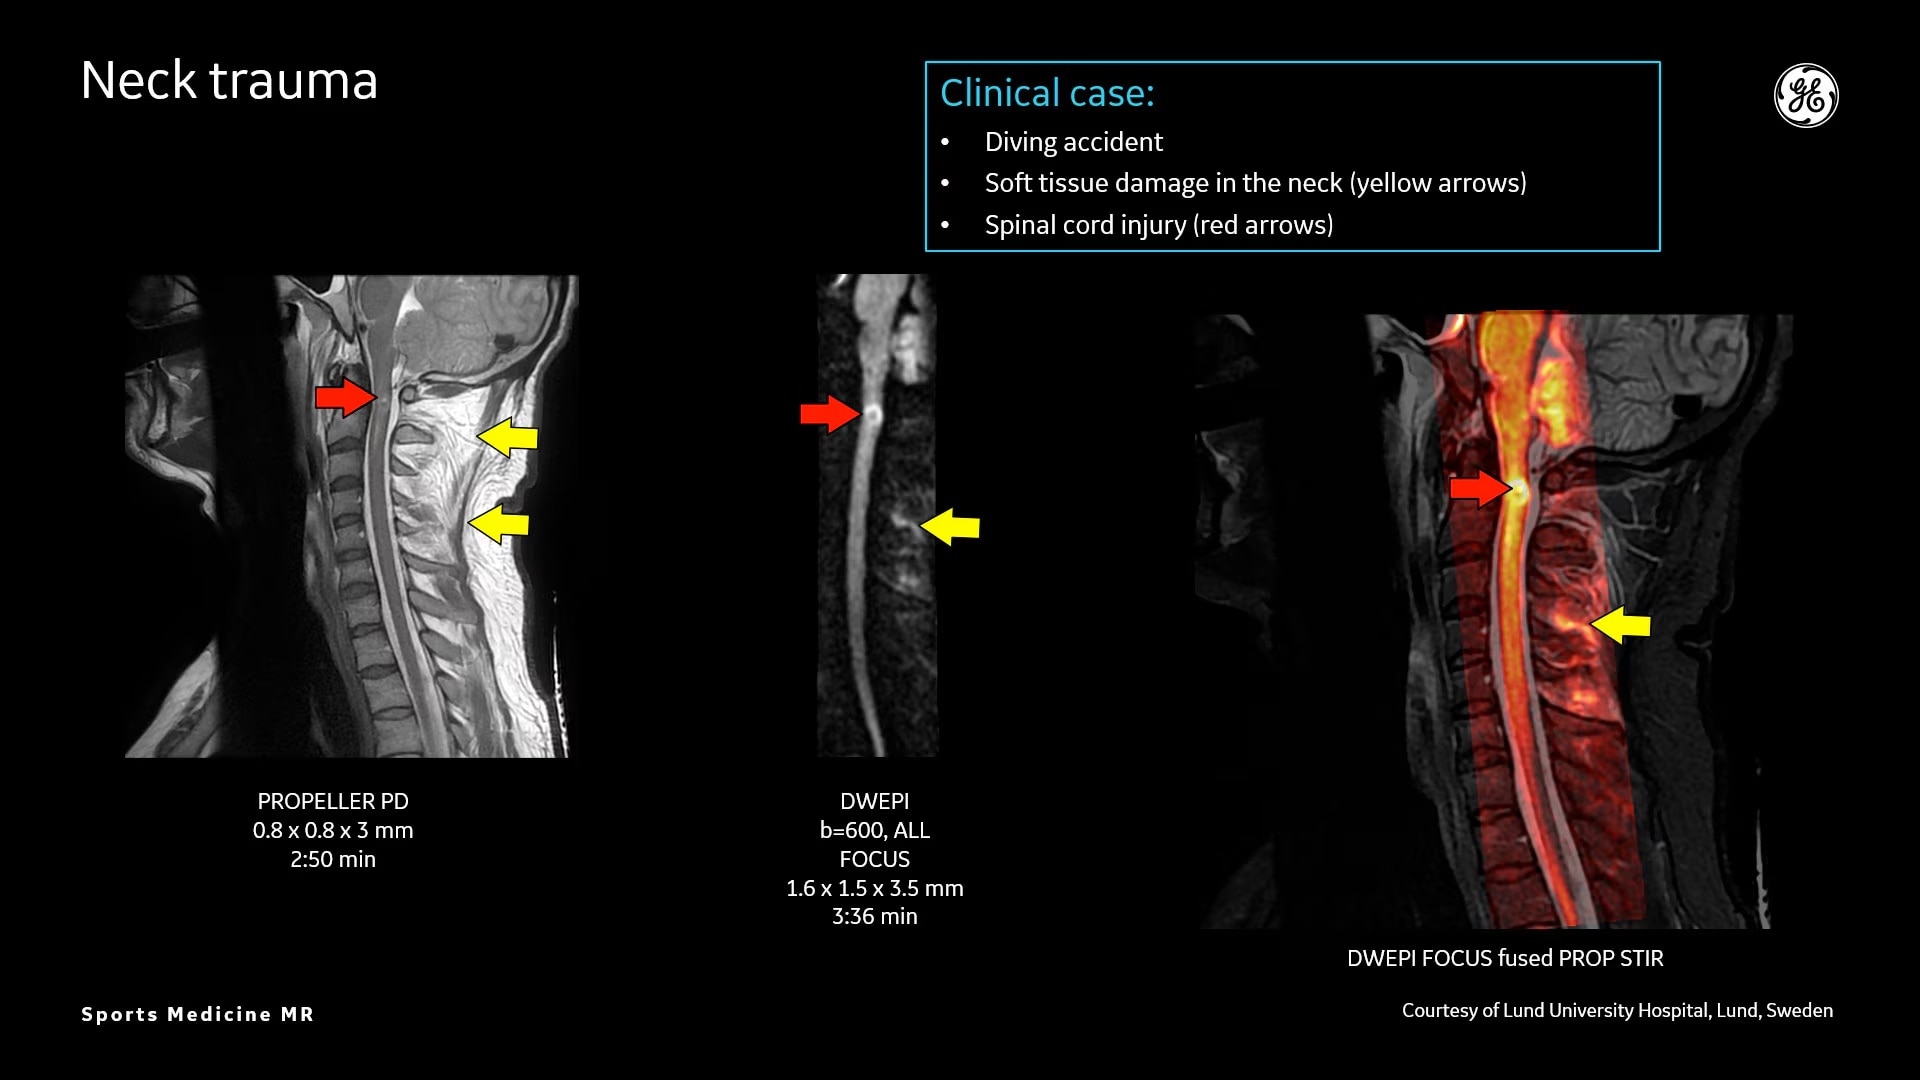

Osseous and Soft-Tissue Injuries

MR bone imaging technology to help diagnose an athlete’s injury

MR lacks ionizing radiation, and is well-suited for longitudinal evaluation of injury in adolescent athletes. The recent introduction of the three dimensional zero-TE (oZTEo) application provides exceptional bone contrast and, like CT, can be reformatted into any arbitrary plane.